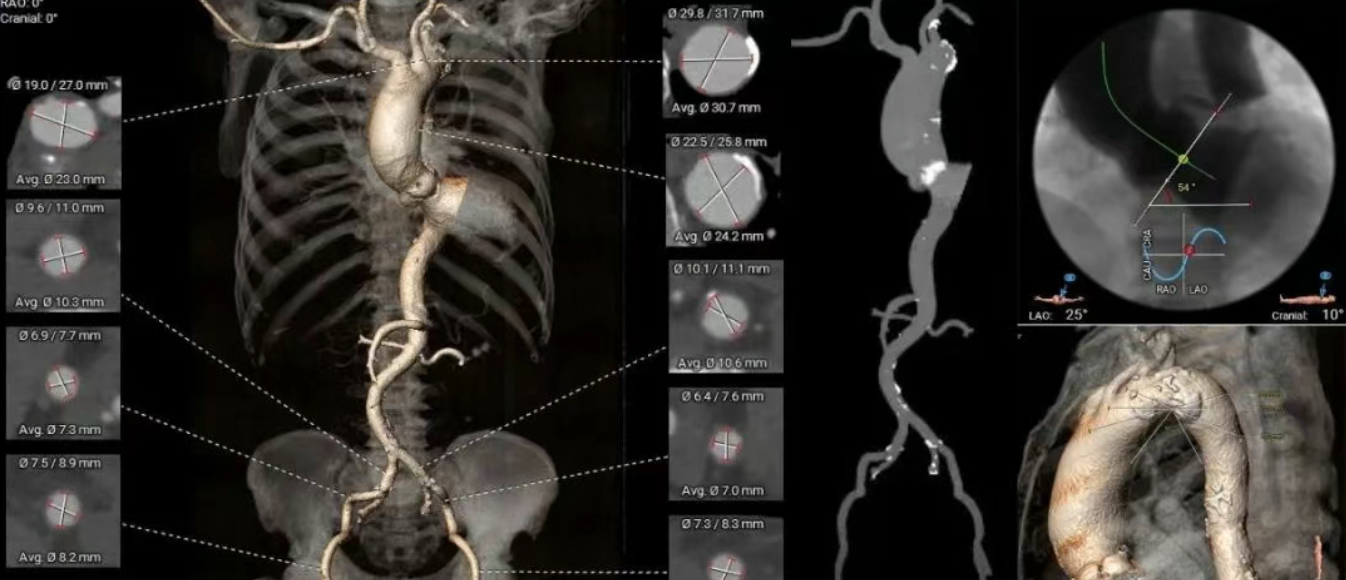

术前CT分析(79岁,男性)

▶ 功能型二叶式主动脉瓣(R-N),瓣叶增厚,重度钙化,钙化分布于左窦瓣叶及右无瓣叶对合缘,LVOT偏敞口型。

▶ 左右冠脉开口高度尚可,左窦瓣叶切线测量距离>冠脉开口下缘到根部距离。

▶ 心室腔内径尚可,心室壁厚度偏厚,心尖偏薄。

▶ 瓣环水平夹角54°,升主动脉扩张,非横位心,主动脉弓部见钙化团块,弓角偏小,弓距尚可。

▶ 外周血管内径可,血管走行稍迂曲,左右侧股动脉中分叉。

主动脉根部测量

瓣上结构测量

冠脉风险评估

LCA Height

RCA Height

左室测量

外周入路评估

手术策略制定

▶ 入路:右侧股动脉植入20F大鞘,左侧股动脉辅入路。

▶ 冠脉:冠脉风险不高,不进行提前保护。

▶ 推荐跨瓣、球囊预扩LAO35°CRA22°(左冠切线)、释放LAO2°CAU22°(左右重合)备用:LAO15°CAU5°(右窦中心)。

▶ 预扩张:20mm球囊。

▶ 瓣膜选型:ScienCrown TF25瓣膜。